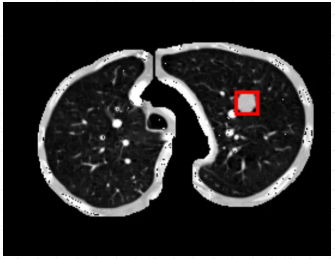

2.1准备数据

关于医疗图像肺结节病灶数据的话,这里本文是利用官方肺结节检测数据集

LUng Nodule Analysis 2016(LUNA16)

进行处理后得到的,已经自己人为标注好了300张病灶数据,可以直接导入华为云ModelArts AI开发平台进行使用。

关于整个肺结节检测数据集的话,数据集文件的大小不大,有35M,共300张已标注好肺结节病灶的文件。